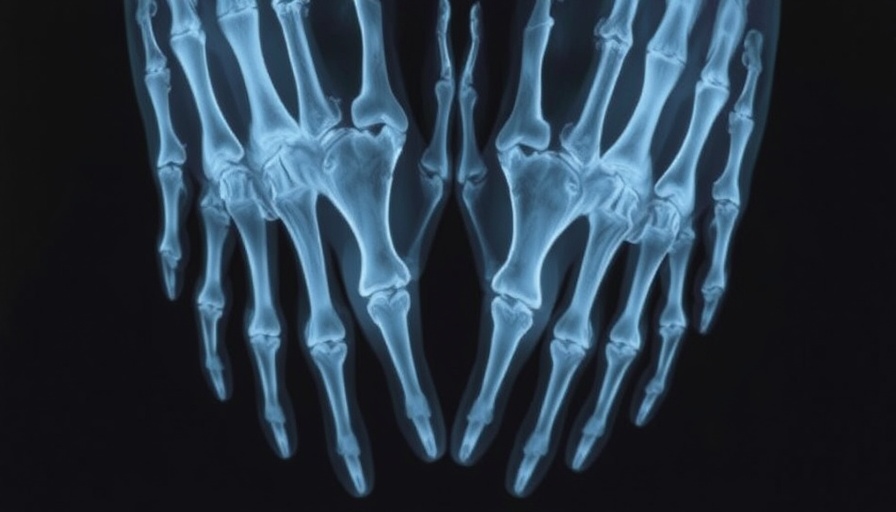

Recent research has raised alarms regarding the discovery of microplastics deep inside human bones, shedding light on a complex health dilemma that is escalating in global importance. With microplastics having infiltrated various facets of our physiology, concerns regarding their implications for bone health have reached critical levels. A meta-analysis led by scientists highlights the presence of microplastics in human bone tissue, linking them to a multitude of health risks, including various bone diseases.

For years, medical practitioners have sounded the alarm over the dangers posed by microplastics. Their effects extend beyond environmental concerns, with recent studies suggesting a direct impact on human bone health. Evidence indicates that microplastics can compromise bone marrow functions, which are vital for the production of blood cells. A breakdown in bone health not only poses risks for fractures and osteoporosis but could also hinder red and white blood cell formation, undermining the body’s immune responses.